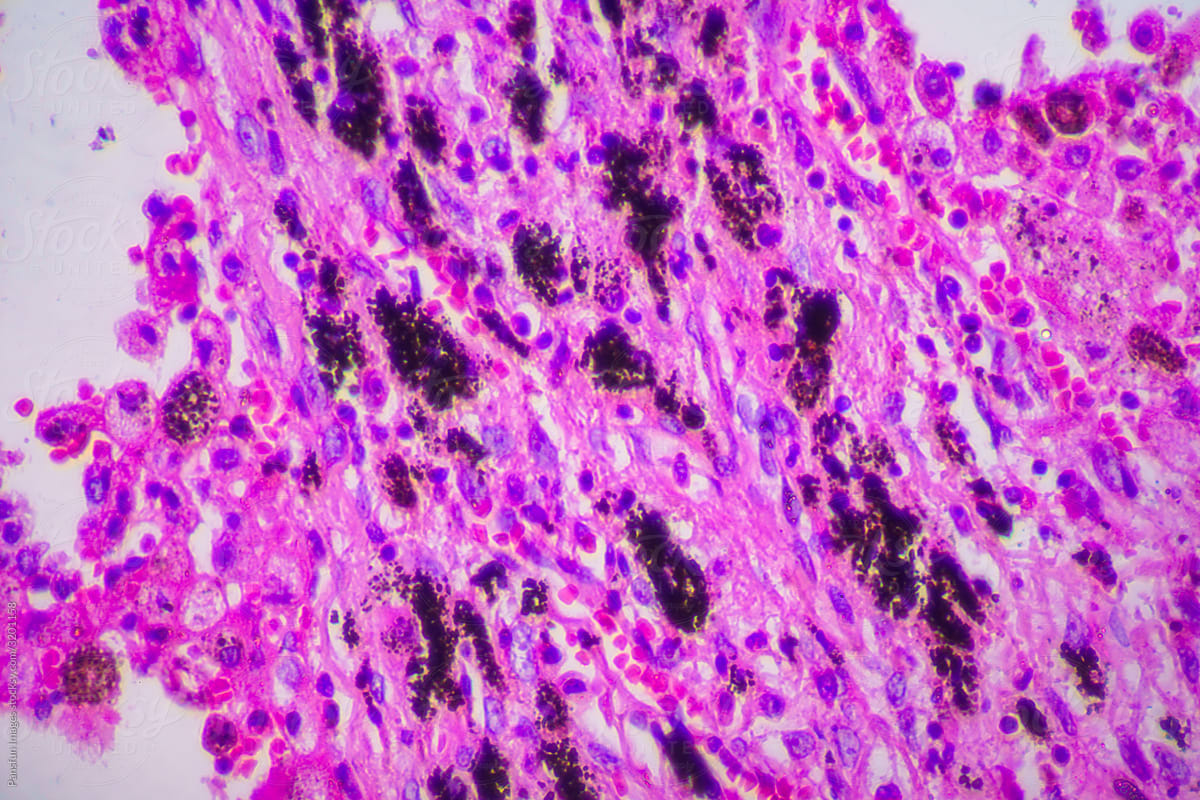

Laboratory Tests and Imaging

Lab tests are key to confirming viral pneumonia. Complete Blood Count (CBC) shows if there’s an infection. Viral PCR (Polymerase Chain Reaction) tests can find the virus. Chest X-rays or CT scans show how much of the lung is affected.

Telling viral from bacterial pneumonia is important. We use symptoms, lab results, and images together. Certain chest images are more common in viral cases.